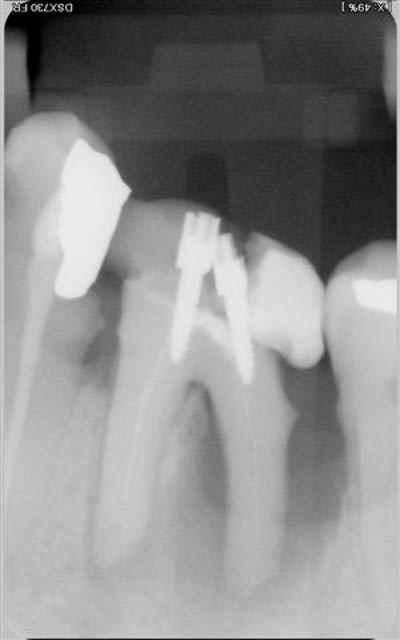

très belles endos ploc!

Pour la lésion endo paro sur la 46, j'aurai certainement extrait d'emblée.

Comme tu as fait un super boulot en endo, autant faire le max en paro maintenant. Il conviendrait de saquer la 48 mésioversée et lors de cette chir décoller un peu en antérieur, surfacer la racine distale et la zone inter radiculaire de la 46. Pas de matériau de comblement car il n'y a plus de paroi osseuse pour le soutenir.

Je reste tout de même pessimiste pour cette dent étant donné qu'il semble y avoir du tartre sur toute la hauteur de la racine distale. Quelle est la possibilité de réattache dans ce cas??? noah?

Je pense qu'il est bon de rappeler que tous nos actes endodontiques et parodontaux (pour ne citer qu'eux) sont basées sur des principes biologiques, qu'il est impossible de contourner.

La cicatrisation parodontale a largement été décrite et repose sur plusieurs impératifs cellulaires : présence de paroies osseuses, présence d'un ligt parodontal intact. Est ce des éléments présents dans le cas présenté .... non.

Tu peux toujours combler avec de la poudre de perlinpimpin, mais dépêches toi de faire une radio juste à la fin de ta chir, c'est le seul moment où tu auras le sentiment d'avoir régénéré de l'os !!

Il est tout aussi important de parler de pronostic que de parler de diagnostic. Et il y a des fois où l'extraction est la seule issue...